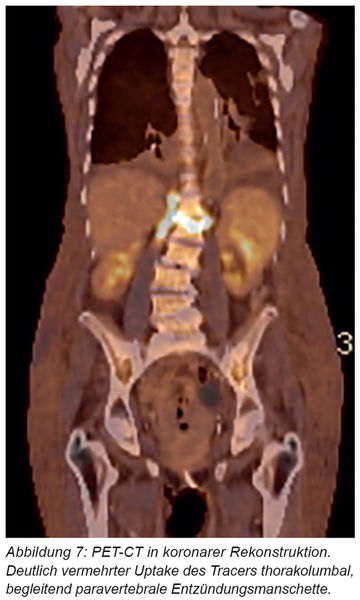

Zum Ausschluss einer Endokarditis führten wir eine transthorakale Echokardiographie und eine transösophageale Echokardiografie durch, zudem bei suspektem Befund an der Mitralklappe noch ein PET-CT. Darin ergab sich kein Hinweis auf eine Endokarditis, der Befund der Spondylodiszitis auf Höhe BWK 12/LWK 1 mit entzündlicher Infiltration im rechten Musculus psoas und entsprechend großflächiger Tracermehrbelegung in den angrenzenden Grund- und Deckplatten, dem Zwischenwirbelraum und perivertebral wurde bestätigt (Abbildung 7).

Gleichwertig zum MRT wird die Fluor-18-Fluorodesoyglucose Positronenemissionstomografie (18F-FDG-PET-CT) gesehen, wobei die PET bei der Unterscheidung zwischen degenerativen und entzündlichen Veränderungen Vorteile aufweist. Physiologisch reichert sich die entsprechend markierte Glukose nicht im Knochenmark und an den knöchernen Strukturen der Wirbelsäule an, sodass sich entzündliche Prozesse mit erhöhter Glukoseaktivität im PET-CT als „hot spots“ (Abbildung 7) darstellen. Im vorgestellten Fall konnten mittels PET-CT weitere Entzündungsherde (zum Beispiel Endokarditis) als mögliche Quellen der Spondylodiszitis ausgeschlossen werden.